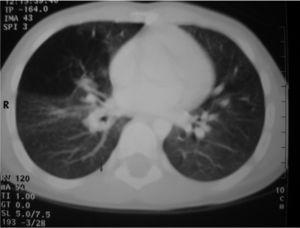

Entre las pruebas complementarias realizadas el electrocardiograma, hemograma y bioquímica no presentaban alteraciones. En la radiografía de tórax se observaba una masa de contornos lobulados, bien delimitada en mediastino superior que originaba ensanchamiento bilateral; en la tomografía computarizada (TC) torácica con contraste (fig. 2) se visualizaba una masa de densidad agua, sin verse adenopatías, la lesión se consideró compatible con quiste de duplicación. En el parénquima pulmonar se observaba una hiperaireación del lóbulo medio con imágenes quísticas alternando con parénquima normal que podría corresponder a malformación adenomatoidea quística o enfisema lobular congénito (fig. 3). El tránsito digestivo superior mostraba una compresión en el tercio inferior de esófago por una masa paratraqueal derecha y en la esofagoscopia no se vio comunicación con la luz esofágica.

Figura 2.TC torácica con contraste: masa de densidad agua, no se ven adenopatías, lesión compatible con quiste de duplicación.